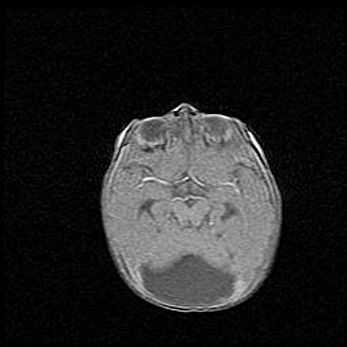

Открытая гидроцефалия.

Возраст: 6 месяцев 15 дней

Вес: 6200 г

Пол: женский

Окружность головы: 41 см

Срок гестации: 38 недель

Гидроцефалия головного мозга у новорожденных – это скопление избыточного количества цереброспинальной жидкости в головном мозге. Ее избыточное скопление в мозге приводит к патологическому расширению желудочков мозга (четырех полостей, расположенных в глубине белого вещества мозга, заполненных цереброспинальной жидкостью и связанных узкими проходами).

Открытый тип гидроцефалии (сообщающаяся) наблюдается тогда, когда нарушен механизм всасывания ликвора в системный кровоток. При этом типе причиной заболевания чаще всего является перенесенные ранее инфекции (например: менингит),  либо же наличие крови в субарахноидальном пространстве.